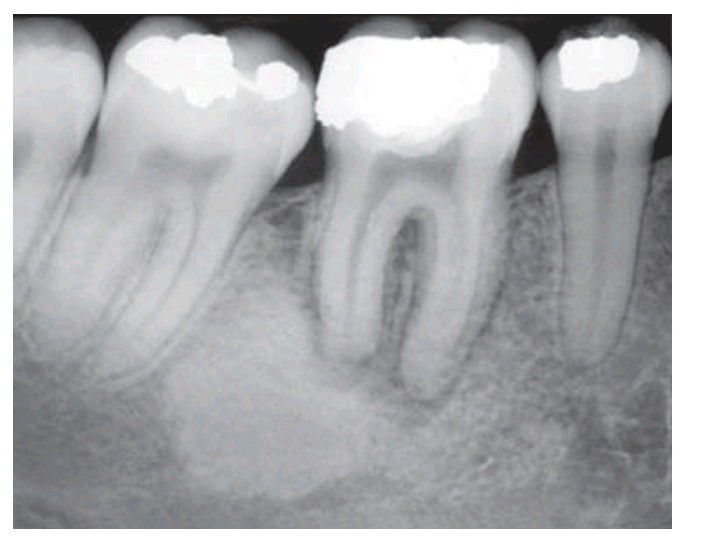

Sclerosing osteitis, a focal zone of sclerosis associated with periapical infl ammation from a non-vital lower fi rst molar.